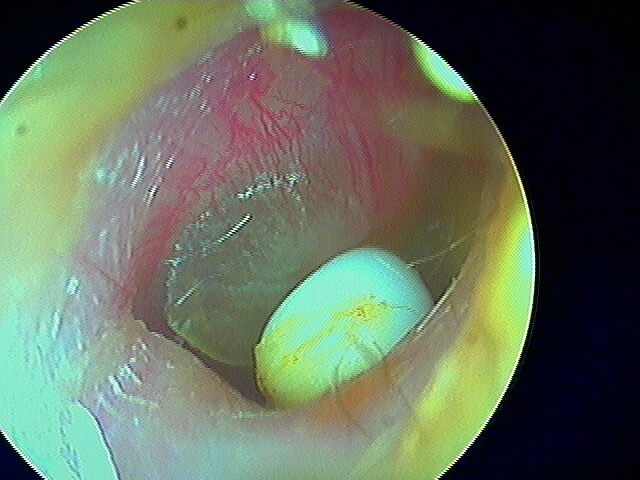

2/7 corps étrangers du CAE

De toutes formes et constitutions (et pas que chez l'enfant! L' aïl est fréquen chez l'adulte!): ici une perle. Je les enlève à la micro-pince/crochet avec une lumière frontale. Chez les enfants, quand je n'y arrive pas, j'utilise l'irrigateur d'eau (notamment une fois pour un pois chiche!).

Après abaltion, le tympan est non perforé non infecté.

Ici le tympan est perforé et infecté après ablation de cette boucle d'oreille, chez un·e adulte.

Encore une perle: